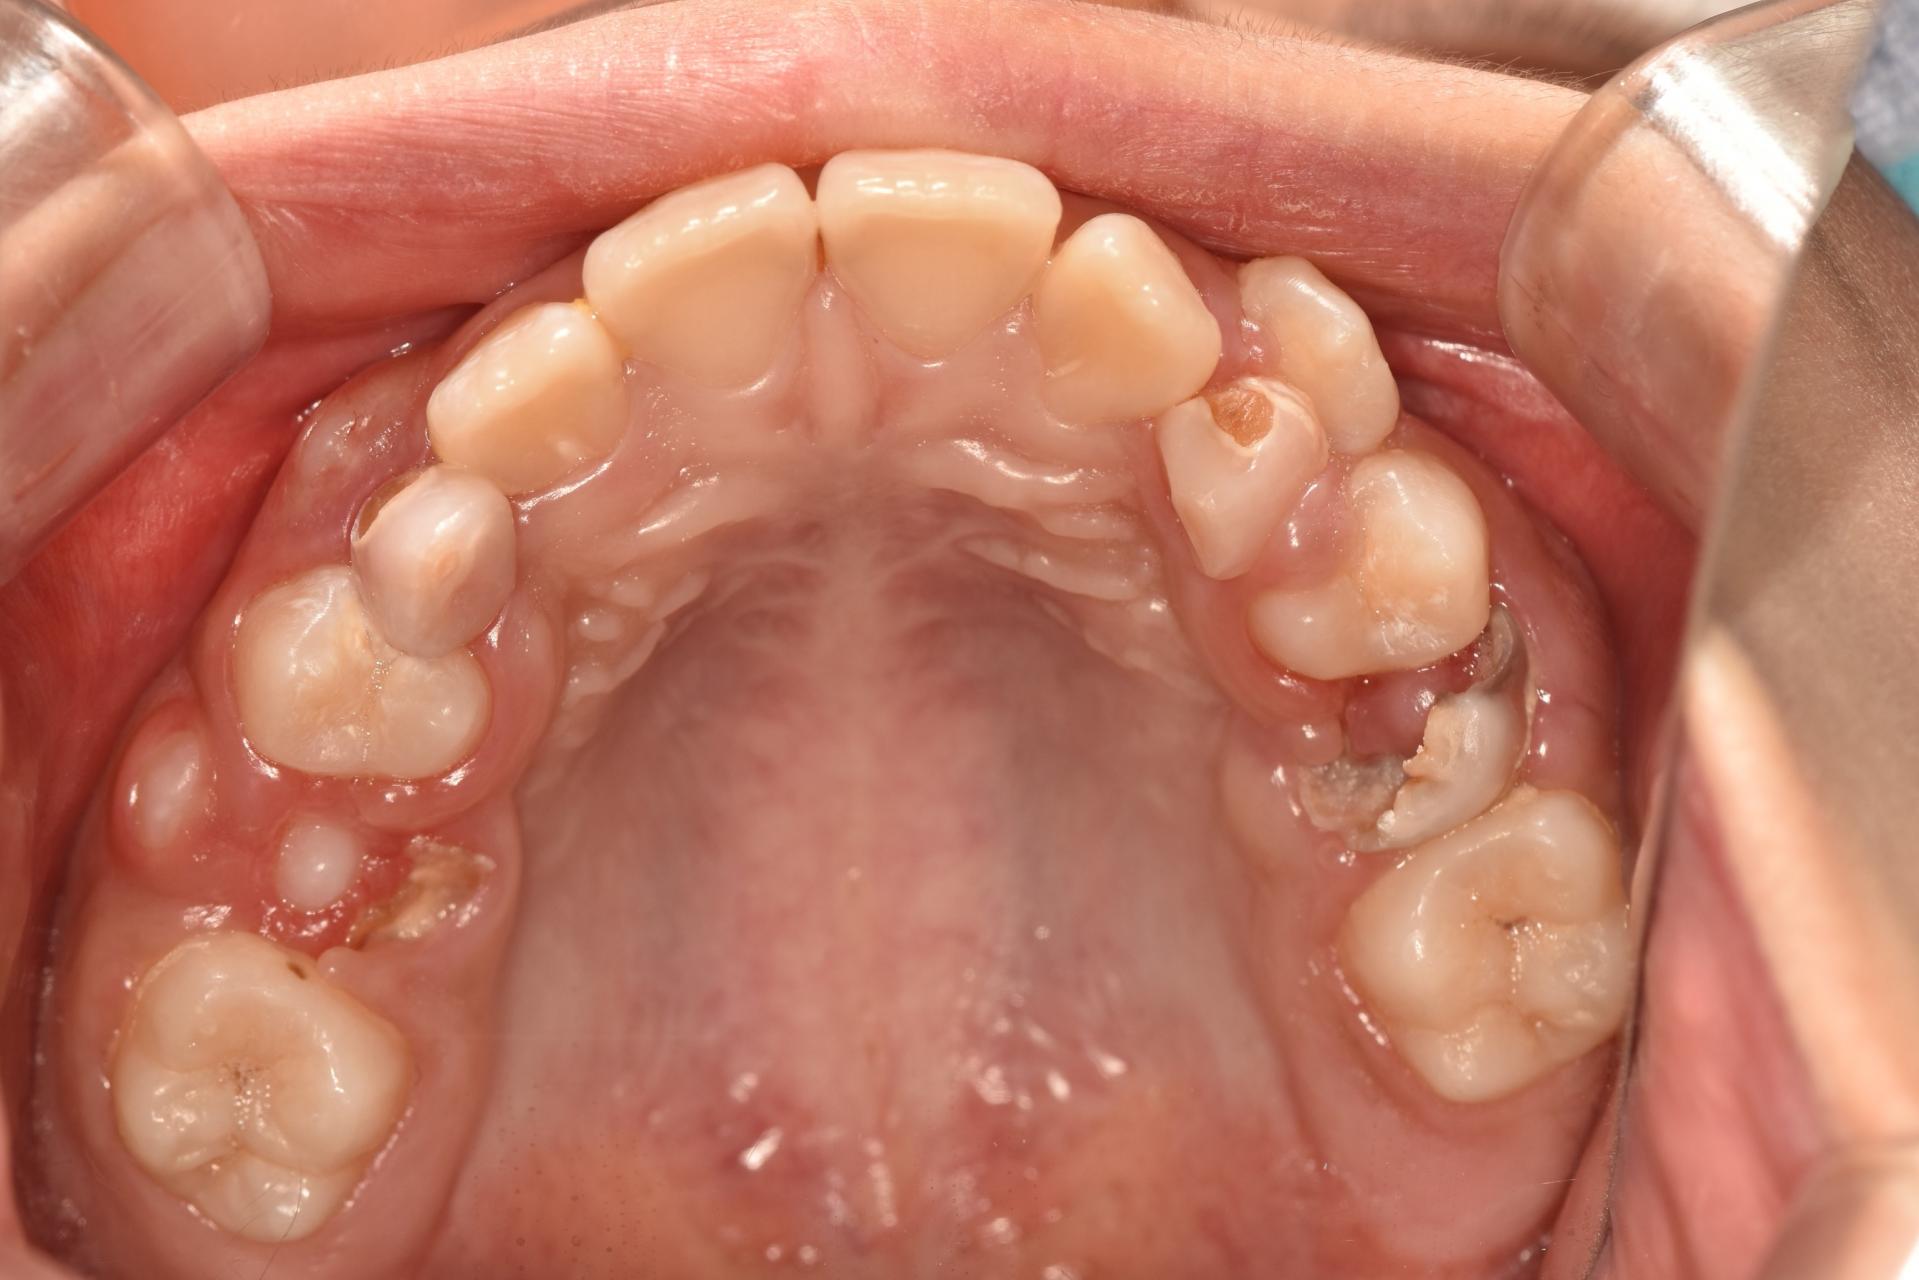

환아의 치료 전, 엑스레이와 구강 내 사진입니다. 거의 모든 치아에 충치가 있습니다. 특히 아래 어금니는 치아의 절반 넘게 충치로 깨져 없어진 상태입니다. 무서워서 빼야 할 시기를 한참 넘긴 남아있는 유치들도 많습니다. 그리고 영구치 윗니 앞니에 사이 충치가 보이네요.